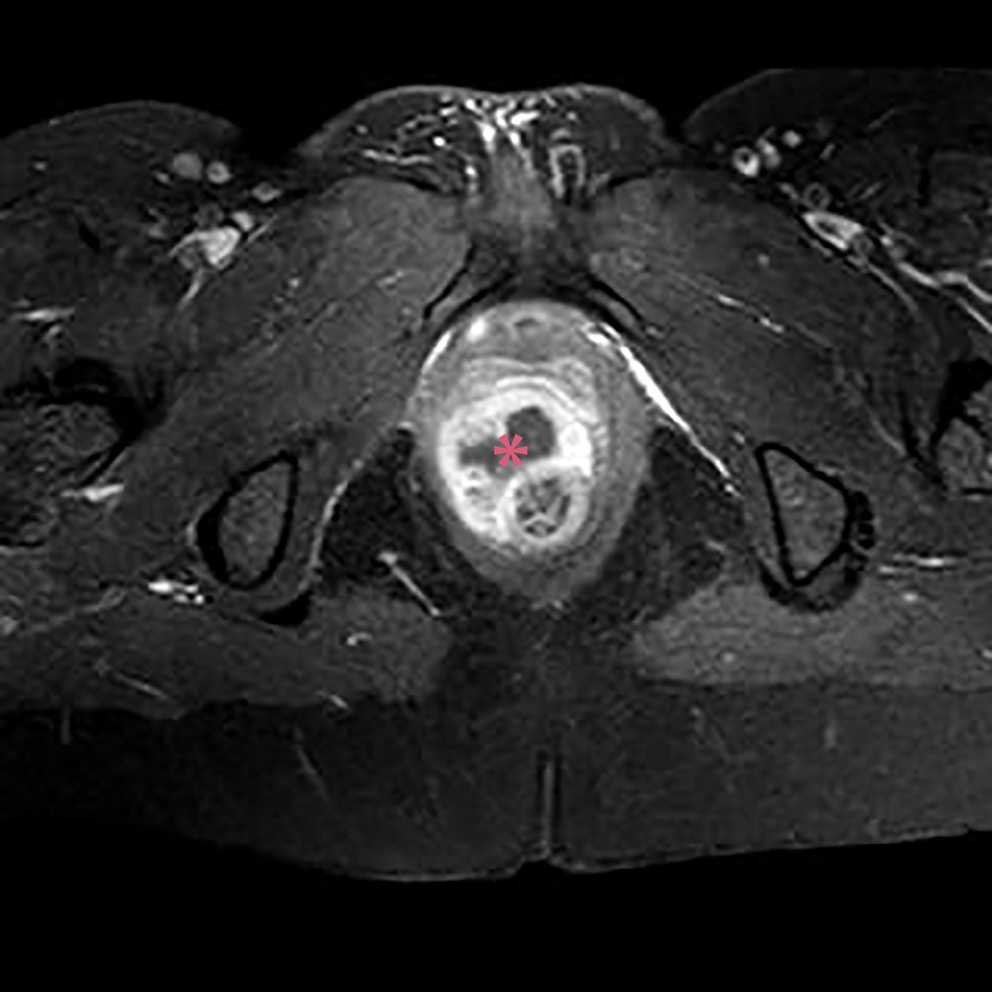

Of the 114 patients included in the study, 78 had complex chronic anal fistulas, and 36 had anorectal abscesses accompanied by anal fistulas. As a result of the MRIs performed in the anorectal abscess group, perianal abscesses were detected in 14 (58%) patients (Figure 2A,B), ischiorectal abscesses in 6 (25%) patients (Figure 3A,B) and intersphincteric abscesses in 4 (17%) patients (Figure 4). Suprasphincteric fistulas were observed in 3 patients, extrasphincteric fistulas were found in 2 patients, horseshoe fistulas were present in 2 patients (Figure 5A,B), and transsphincteric fistulas were observed in the remaining patients with complex fistulas. Thirteen patients had 2 external fistula ora and 4 patients had 3 external fistula ora. Eight patients in the fistula group had an abscess pouch associated with the fistula tract. These findings are consistent with the literature.